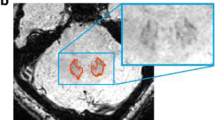

Dentate nuclei (DNs) segmentation is helpful for assessing their potential involvement in neurological diseases. Once DNs have been segmented, it becomes possible to investigate whether DNs are microstructurally affected, through analysis of quantitative MRI parameters, such as those derived from diffusion weighted imaging (DWI). This study developed a fully automated segmentation method using the non-DWI (b0) images from a DWI dataset to obtain DN masks inherently registered with parameter maps. Three different automatic methods were applied to healthy subjects: registration to SUIT (a spatially unbiased atlas template of the cerebellum and brainstem), OPAL (Optimized Patch Match for Label fusion) and CNN (Convolutional Neural Network). DNs manual segmentation was considered the gold standard. Results show that SUIT results have a Dice Similarity Coefficient (DSC) of 0.4907±0.0793 between automatic and gold standard masks. Comparing OPAL (DSC = 0.7624±0.1786) and CNN (DSC = 0.8658±0.0255), showed that a better performance was obtained with CNN. OPAL and CNN were optimised on high spatial resolution data from the Human Connectome Project. The three methods were then used to segment DNs of subjects with Temporal Lobe Epilepsy (TLE) from a 3T MRI research study with DWI data acquired with a coarser resolution. In TLE, SUIT performed similarly, with a DSC = 0.4145±0.1023. OPAL performed worse than using HCP data with a DSC of 0.4522±0.1178. CNN was able to extract the DNs without need for retraining and with a DSC = 0.7368±0.0799. Statistical comparison of quantitative parameters from DWI analysis, as well as volumes, revealed altered and lateralised changes in TLE patients compared to healthy controls. The proposed CNN is a viable option for accurate extraction of DNs from b0 images of DWI data with different resolutions and acquired at different sites.